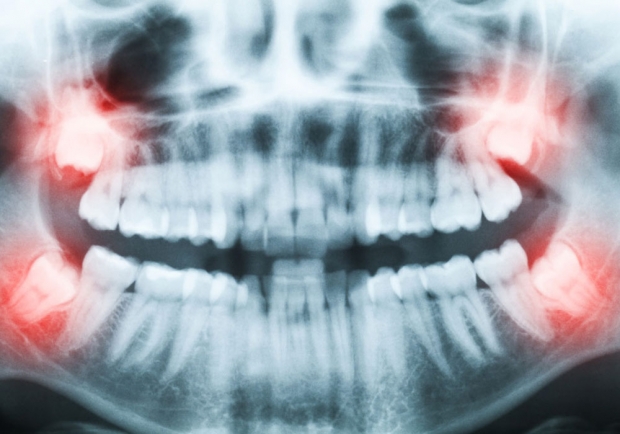

Chirurgies mineures (ex : dents de sagesse)

Les dents de sagesse, aussi appelées troisièmes molaires, sont les dernières dents à se développer. Elles présentent une grande variété de forme et de taille selon les individus. Elles sont positionnées complètement à l’arrière de la dentition, derrière les 2e molaires.

Les dents semi-incluses sont difficiles d’accès et donc impossible à nettoyer adéquatement. Les bactéries et les débris alimentaires restants peuvent causer plusieurs problèmes, notamment des caries.

Les dents incluses augmentent les chances de développer un kyste ou une tumeur bénigne.

Les dents incluses et semi-incluses peuvent causer des maladies localisées de la gencive et de l’os entourant ces dents.

La péricoronarite (inflammation des tissus entourant la couronne de la dent) et la cellulite (une infection des tissus mous du visage) sont des complications possibles des dents de sagesse incluses ou semi-incluses.